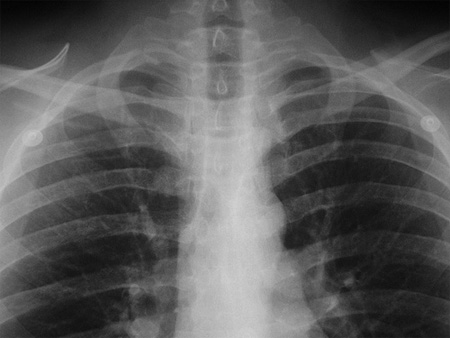

pls i need to see a doctor for respiratory infection but i dont have an insurance